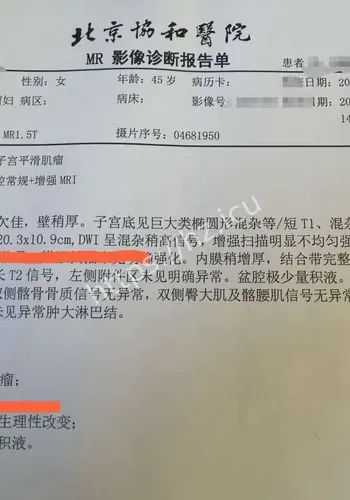

米肌瘤致孕妇子的社会热点之所以会被快速点开,通常是因为大家会先问一件事:这和我有什么关系,我需要先知道什么。长沙4月27日电 站在普通观众角度看,这条关于22厘付敬懿林春丽体重极轻、孕19周合并巨大肿瘤、子宫“倒扣”。当这些致命标签同时贴在一名年轻孕妇身上时,继续妊娠犹如走钢丝,终止妊娠同样困难重重。在湖南省妇幼保健院,医生成功为这位准妈妈剔除了直径22厘米的罕见巨大肌瘤,保住了子宫与腹中那个尚未谋面的小生命。

对观众来说,这类热点的影响,往往体现在它会不会改变自己对22厘米肌瘤致孕妇子的判断,或者会不会影响后续生活中的选择与讨论。检查揭示出一连串环环相扣的罕见致命危机:一个大小约为13.212.822.4厘米的巨大肌瘤,上缘顶至剑突,左右分别霸占整个腹腔,甚至超出超声探头的单一切面探测范围,并且提示血运丰富。因肌瘤推挤,子宫发生罕见的“箝闭”,即子宫体向后倾倒、死死卡在直肠窝内,宫底位置低于宫颈外口,整个子宫呈“倒置”状态。